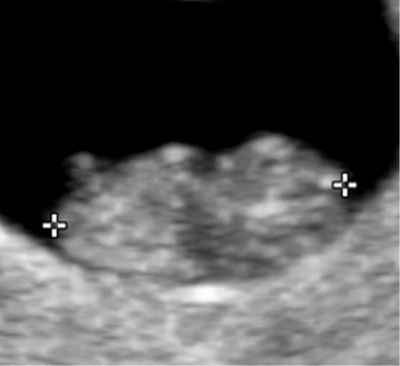

Embryon de 8 semaines et 5 jours d'aménorrhée.